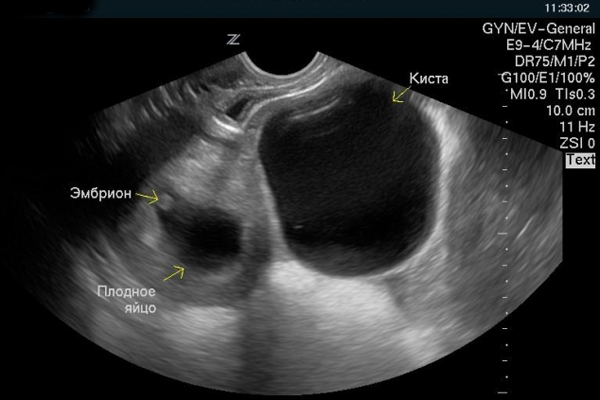

На фото ниже показано УЗИ беременности при кисте.